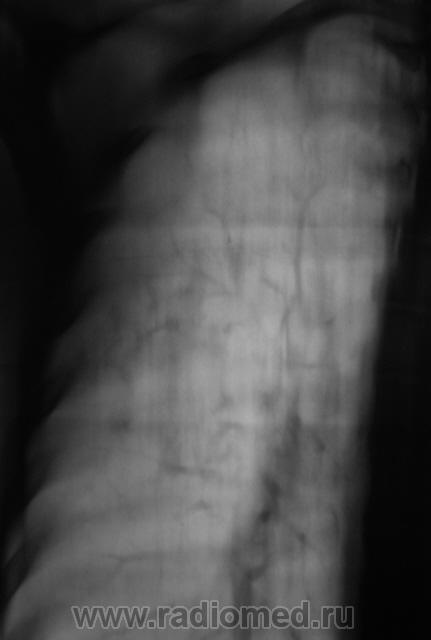

Произвели цифровую флюорографию, сразу посмотрел и "взяли на контроль". Произведена рентгенография в прямой и правой боковой проекциях. Со слов пациента, он никогда и ни чем не болел, туб. кабинету не известен.

ИзображениеИзображениеИзображение